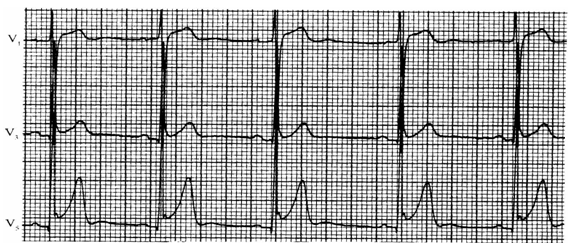

图1 第1-7列分别为高钾血症、左束支传导阻滞、左心室肥厚、Brugada综合征、急性心包炎

和急性前间壁心肌梗死(第6、7列)

左束支传导阻滞:V1-V3导联ST段凹形抬高,S波或QS波越深ST段抬高程度越明显;ST段方向与QRS主波相反,QRS时限大于0.12 s;T波高耸,ST-T改变持续存在。

左心室肥厚:可表现为V1-V3导联ST段凹形抬高;V1-V3导联S波越深,右胸导联ST段抬高程度越明显,可达0.5mV以上;V4-V6导联ST段下降。

Brugada综合征:右胸导联ST段抬高,呈下斜型、马鞍型或混合型抬高,一般局限于V1、V2导联;ST段抬高起始于R或R'波顶部,并出现T波倒置;对应导联无ST段压低,伴或不伴有束支传导阻滞,无动态演变过程,Q-T间期正常。